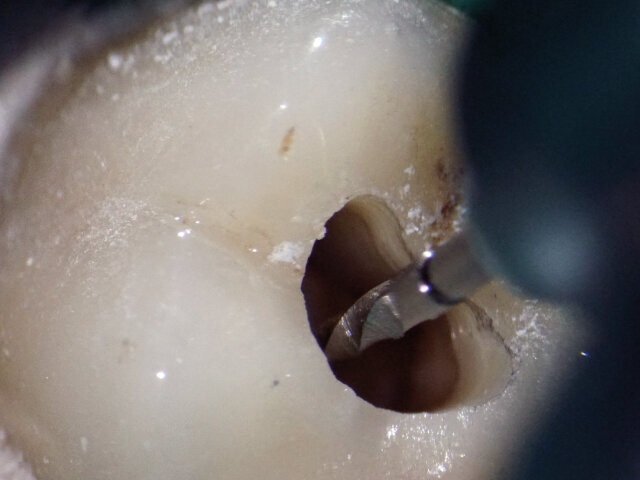

K rozšíření kanálků byly použity nástroje ProTaper Gold (obr. 4) (MB1 velikostí F2, DB velikostí F1 a P velikostí F4).